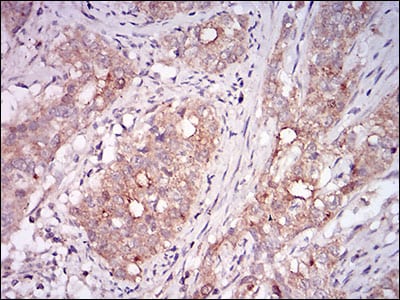

分类: 科研抗体货号: 30622别名: GDF8; MSLHP应用: IHC反应种属: Human